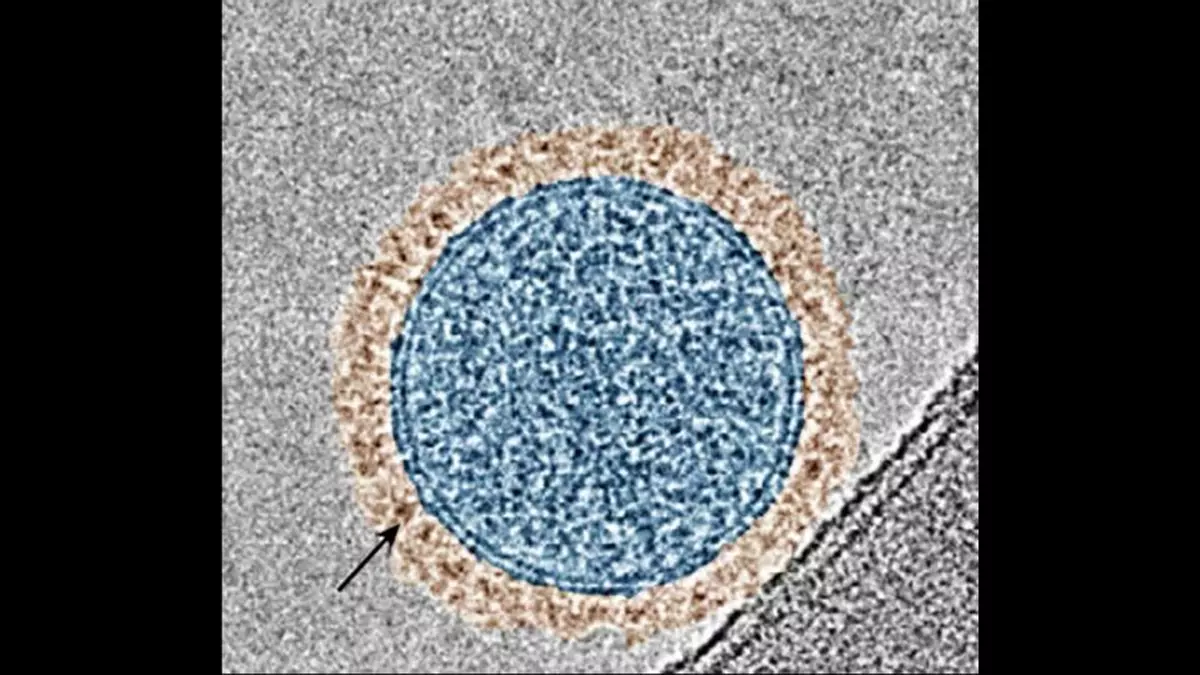

Investigadores de la Universidad de Columbia han desarrollado una nanoterapia inhalable que puede activar el sistema inmunitario contra cánceres resistentes a las terapias actuales con inhibidores de puntos de control. BEAT (Activador Biespecífico de Exosomas de Células T), que utiliza pequeñas burbujas, llamadas exosomas, para administrar proteínas terapéuticas directamente a los pulmones, el sitio de metástasis no cutánea más común en el melanoma.

“A diferencia de los fármacos de anticuerpos existentes que bloquean un solo punto de control inmunitario, BEAT utiliza exosomas modificados (vesículas nanométricas del propio cuerpo) para bloquear simultáneamente dos vías que suprimen el ataque inmunitario”, afirmó Ke Cheng, profesor Alan L. Kaganov de Ingeniería Biomédica en Columbia Engineering. “El método de ingeniería de exosomas en tándem abre una nueva vía para administrar múltiples proteínas terapéuticas localmente, una plataforma que podría aplicarse a enfermedades autoinmunitarias, infecciosas o fibróticas donde se requiere una modulación multidiana”.

Durante los últimos 15 años, el Laboratorio Cheng ha estado desarrollando exosomas para su uso como transportadores de fármacos con un perfil de biocompatibilidad y seguridad favorables. Los investigadores han desarrollado recientemente una terapia de inhalación mediada por exosomas para diversas enfermedades pulmonares, como la COVID-19 y el cáncer de pulmón, así como enfermedades cardiovasculares.

En el estudio actual, Cheng y sus colegas crearon un sistema de exosomas que copresenta dos proteínas terapéuticas para tratar las metástasis pulmonares. Una proteína bloquea la vía de control inmunitario PD-1/PD-L1, un proceso que ha demostrado potenciar la respuesta inmunitaria contra las células de melanoma y reducir el tamaño de los tumores. La otra proteína bloquea la vía de señalización Wnt/β-catenina, que impulsa la exclusión inmunitaria en los tumores, un fenómeno en el que las células inmunitarias no pueden infiltrarse en los tejidos tumorales.